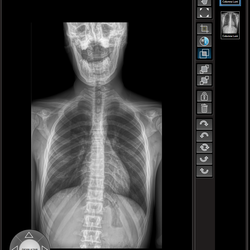

Stitching